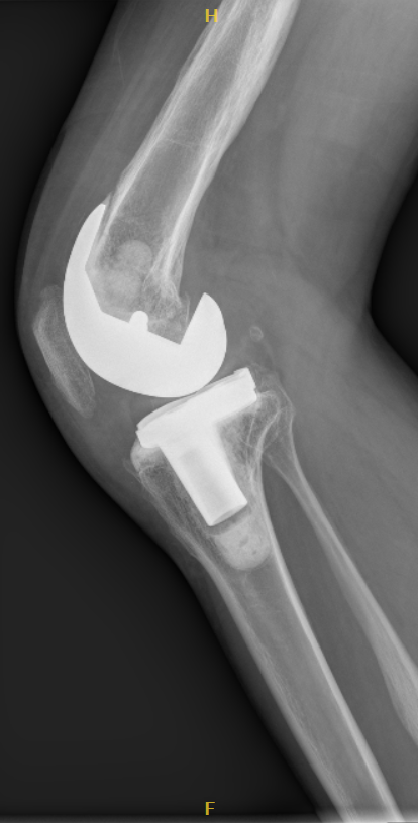

1、术后影像

3、术后3年复查